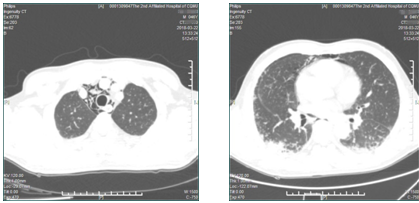

2018年3月6日,重医附二院风湿免疫科收治一名46岁的中年男性患者,因“间断发热2月余,咳嗽、喘累20余天”由外院转入我院。入科后完善相关